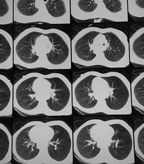

Cancer of the esophagus, CT with contrast, axial image.